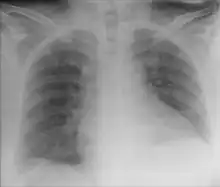

Chest X-ray showing obvious Chilaiditi's sign, or presence of gas in the right colic angle between the liver and right hemidiaphragm.

Chilaiditi syndrome is a rare condition when pain occurs due to transposition of a loop of large intestine (usually transverse colon) in between the diaphragm and the liver, visible on plain abdominal X-ray or chest X-ray.[1]

Normally this causes no symptoms, and this is called Chilaiditi's sign. The sign can be permanently present, or sporadically. This anatomical variant is sometimes mistaken for the more serious condition of having air under the diaphragm (pneumoperitoneum) which is usually an indication of bowel perforation, possibly leading to surgical interventions.